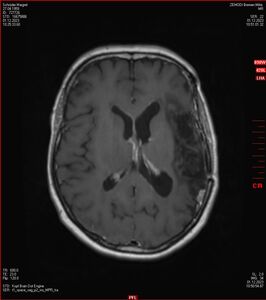

MRT vom 12. November 2024

So nun ein paar neue Bilder aus meinem Kopf. (Durch klicken bekommt man eine größe Ansicht eines Einzelbildes).

Die letzten drei Bilder Zeigen aus meiner Sicht den Tumor, der im Jahr 2021 bestrahlt wurde.